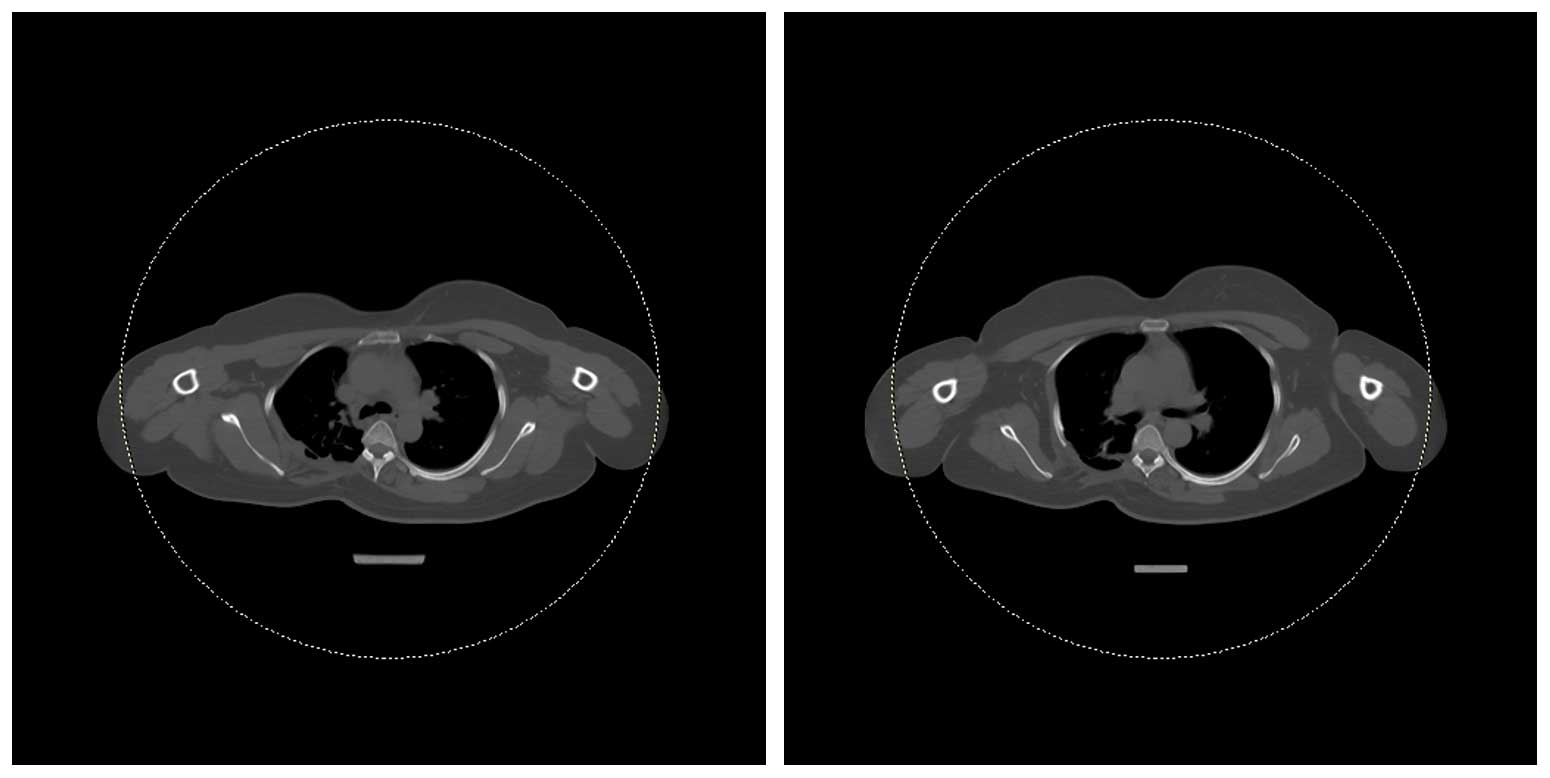

Ameliyat Sonrası: Kontrol tomografi kesitlerinde tümörün tamamen çıkarıldığı görülmekte.